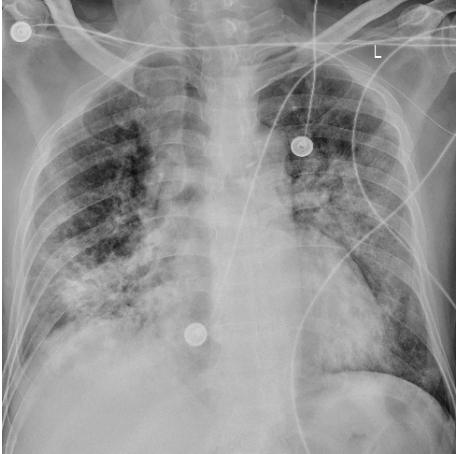

床边胸片可见双肺多发斑片影,考虑双肺感染(图4)

图片

图4 床旁胸片(2023-01-30)